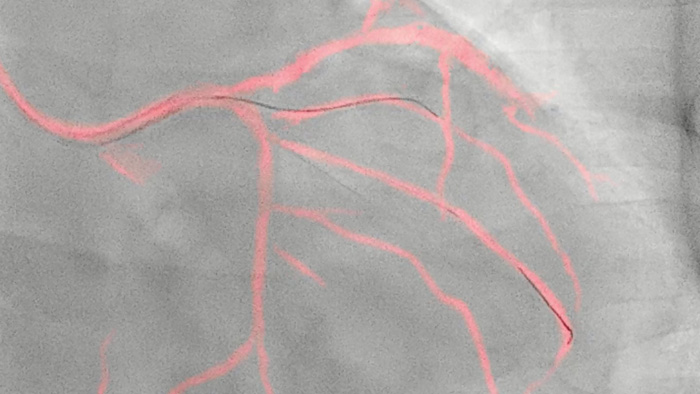

Uma tecnologia exclusiva da Philips cria uma visualização das artérias coronárias em tempo real com compensação de movimento. Um angiograma coronário em destaque é sobreposto a uma imagem fluoroscópica 2D ao vivo, criando um roteiro colorido que se ajusta automaticamente fornecendo um feedback visual contínuo sobre o posicionamento de fios e cateteres.